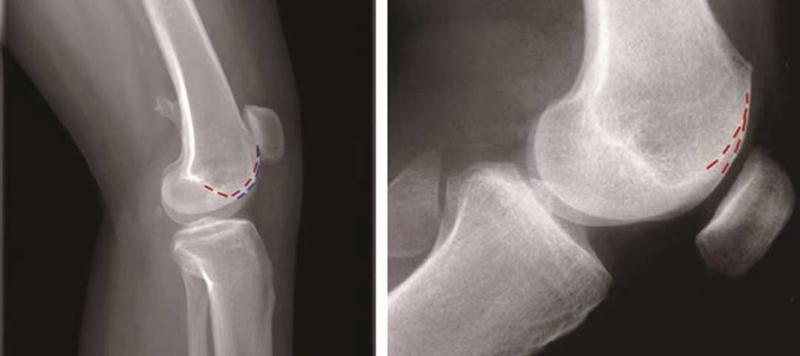

交叉征:

H.Dejour在1987年介绍了股骨滑车发育不良在膝关节标准侧位X线片的特殊表现,描述了交叉征(crossing sign)。在股骨滑车发育不良的膝关节标准侧位像上,股骨滑车沟基底线会与股骨外髁的轮廓线相交叉,即为交叉征(图11),意味着股骨滑车发育平坦。

图11 交叉征